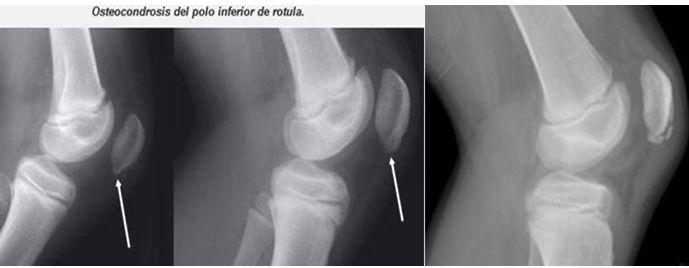

DOLOR EN MIEMBROS INFERIORES.

SEMIOLOGIA DE LOS MIEMBROS INFERIORES